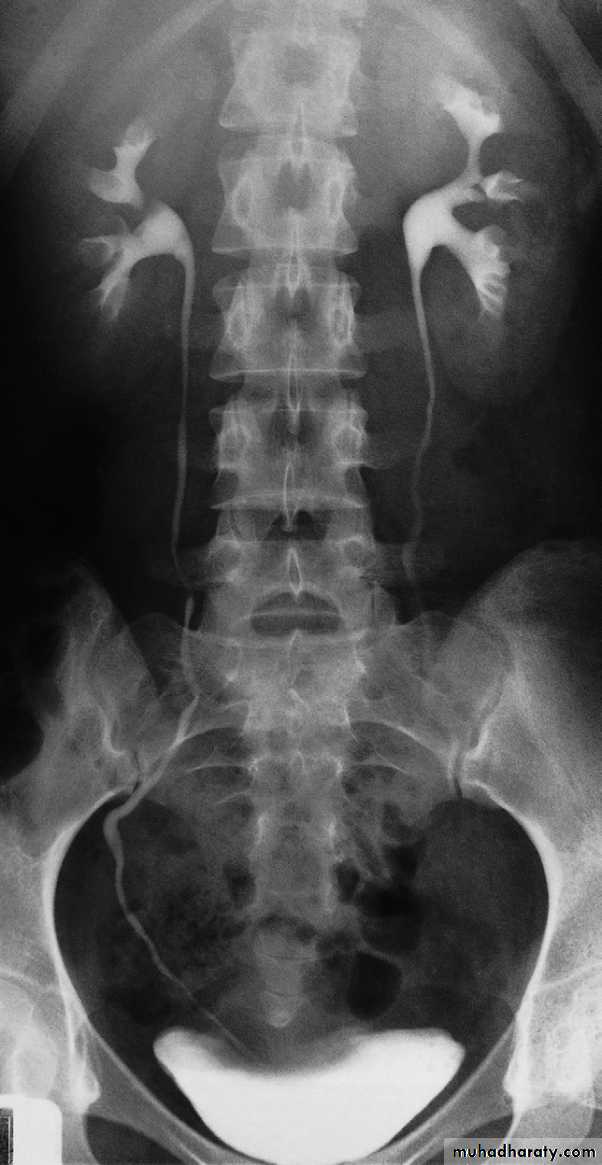

IVU study

-Plain film in intravenous urogram: it used to Identify all calcifications. Decide if they are in the kidneys by relating them to the renal outlines , calcification seen in the line of the ureters or bladder must be reviewed with post contrast scans, to determine whether the calcification lies in the renal tract. Note that calcification can be obscured by contrast medium and stones are missed if no plain film is taken.-Films taken after injection of contrast medium Kidneys

1 .Check that the kidneys are in their normal positions . The left kidney is usually higher than the right.2 .Identify the whole of both renal outlines. If any indentations or bulges are present they must be explained.

3 .Measure the renal lengths.Calices

The calices should be evenly distributed and reasonably symmetrical. The shape of a normal calix is ‘cupped’ and when it is dilated it is described as ‘clubbed .causes of dilated calcies

pelvis and ureters

The normal renal pelvis and pelvi-ureteric junction are funnel shaped. The ureters are usually seen in only part of their length on any one film of IVU because of obliteration of the lumen by peristalsis.Congenital variations of the renal collecting system are relatively common .

Bladder

The bladder is a centrally located structure that should have a smooth outline. It often shows normal smooth indentations from above owing to the uterus or the sigmoid colon, and from below by muscles of the pelvic floor .After micturition the bladder should

be empty, apart from a little contrast

trapped in the folded mucosa.